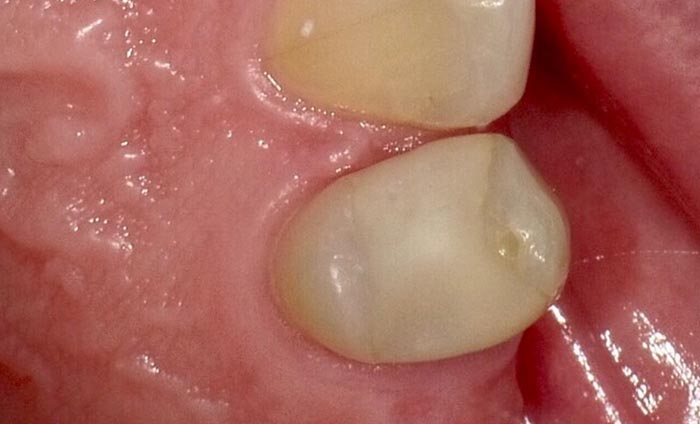

A 37-year-old patient presented for treatment after years of neglect. After administering anesthetic and placing an Isolite isolation device, we prepared teeth #10–12 and restored them

with Activa Bioactive-Restorative composite.

• Figure 2